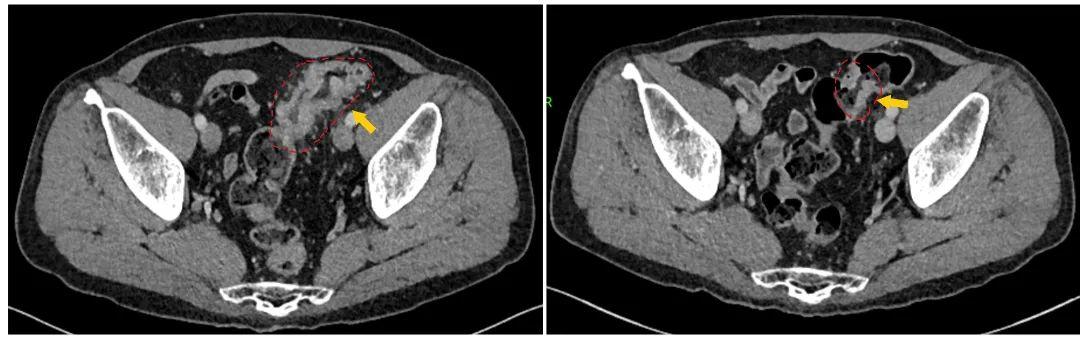

初诊时肿瘤较大,侵犯周围脂肪组织

化疗后肿瘤明显缩小

手术后肿瘤消失